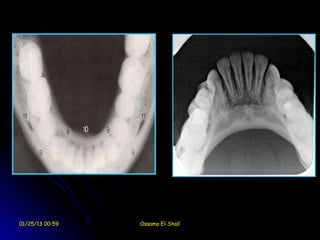

Occlusal films

Occlusal films are use to radiographically

clarify the anatomical structures and

the pathological conditions of the

maxilla or mandible in the bucco-lingual

dimension.

Occlusal films may use for the following

purposes:

1.     Obtaining gross views for the jaws in the

bucco-lingual dimension.

2.     Detection location and extent of fractures.

3.     Detection of the bucco-lingual direction of

impactions and supernumerary teeth.

4.     Detection of bucco-lingual direction of

displaced fracture.

5.     Detection of salivary gland or duct stone

especially in the mandible.

6.     Localization of foreign bodies such as

broken needle.

7.     Determination of the shape of dental

arches.

01/25/13 00:59        Ossama El-Shall